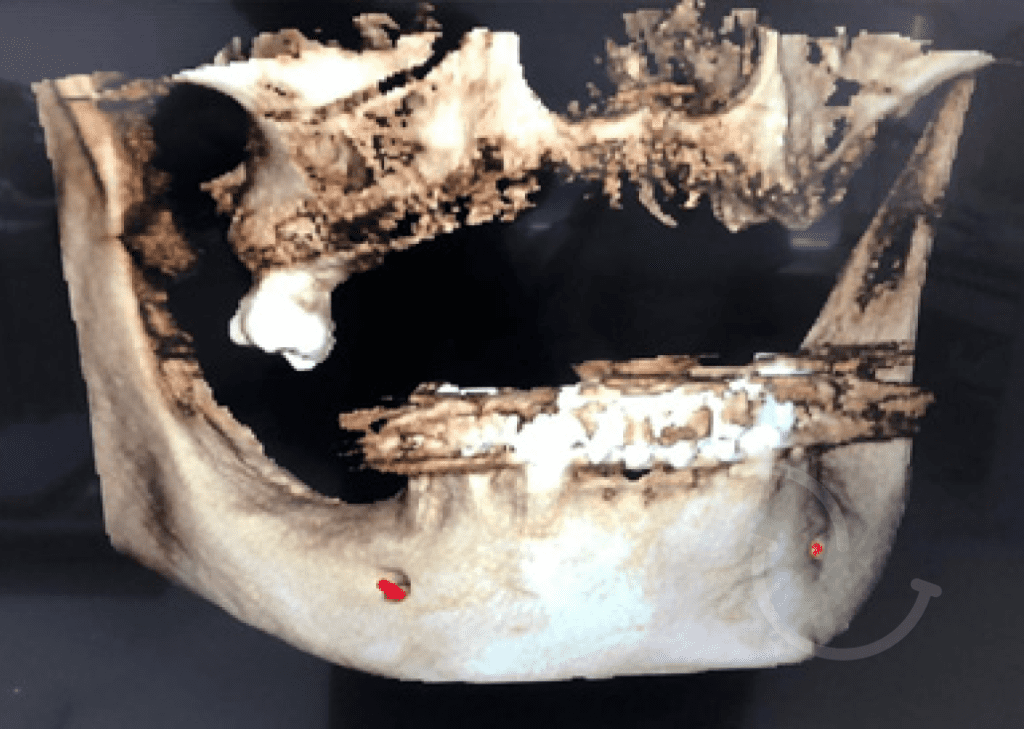

Casos clínicos de implantes dentales